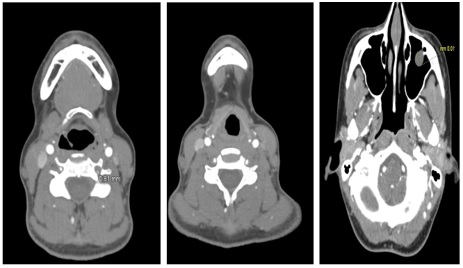

On examination, vital signs were stable, extraocular movements and visual fields were intact, and cranial nerves II-XII were normal. Neck flexion was limited due to pain, but no focal neurological deficits were noted. Given her headache following cervical manipulation, the differential diagnosis included tension headache, migraine, occipital neuralgia, and cervical artery dissection. Laboratory tests, including Complete blood count, Complete metabolic panel, C-reactive protein, erythrocyte sedimentation rate, and ANA screen, were unremarkable (Table 1). CT angiography (CTA) of the head and neck with contrast revealed bilateral vertebral artery stenosis suggestive of vertebral artery dissection (Figure 1). She was started on a heparin drip for anticoagulation, and neurology and interventional neurology were consulted, who recommended conservative management. She was discharged on day three with warfarin therapy and reported improvement in her headache. Follow-up imaging at six months showed healing of the dissections, and she remained neurologically intact. Warfarin was discontinued at her six-month follow-up, and she was transitioned to long-term antiplatelet therapy with aspirin.

Figure 1: CT Angiogram of head and neck showing bilateral vertebral artery stenosis suggestive of dissection.